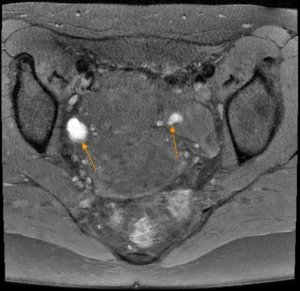

Endométriome bilatéral | |||